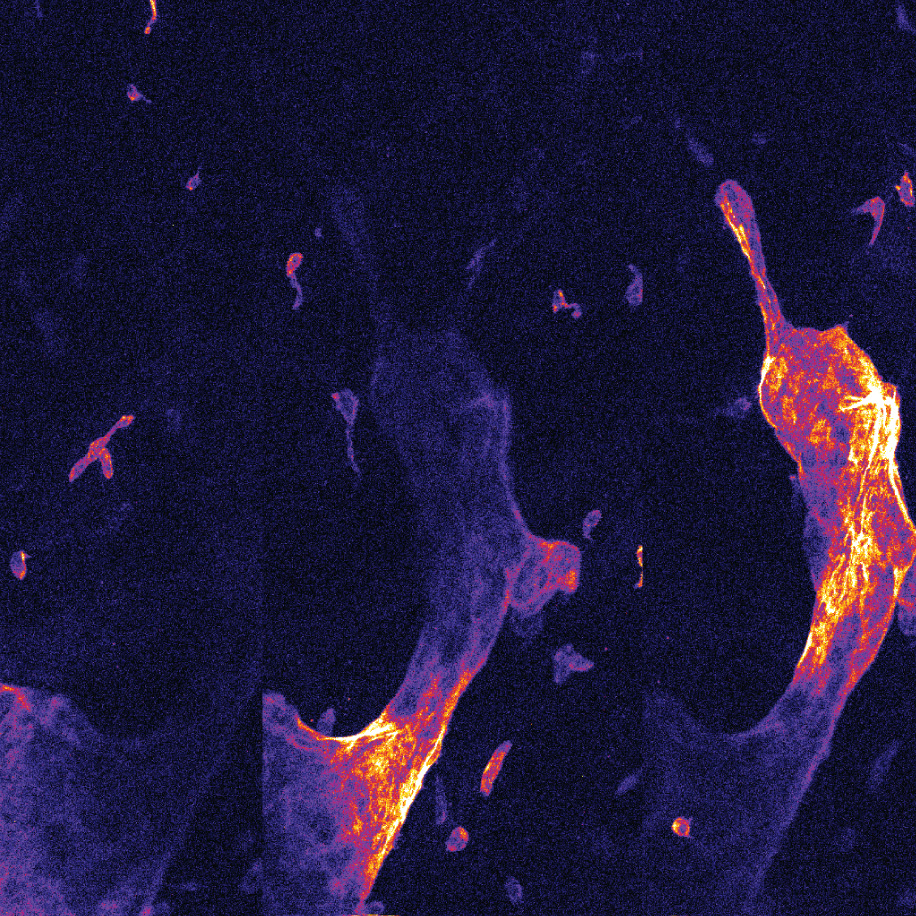

ViewnVivo® offers single-cell level live imaging, providing unique biological system insights and enabling users to see life connected. Developed with our patented confocal imaging technology, ViewnVivo® is a miniaturized in vivo imaging device that offers single-cell 3D live microscopic imaging in the palm of your hand.

Designed specifically for life sciences, pre-clinical and translational research, ViewnVivo® enables users to see systems biology in harmony, maintaining key cell structures, biological systems and cell-to-cell interactions to provide valuable translational results to accelerate drug discovery or unlock new study possibilities.

Easy to work on live tissues. - Image depth variation

Images can be easily post-processed to produce a range of presentations (incl 3D).